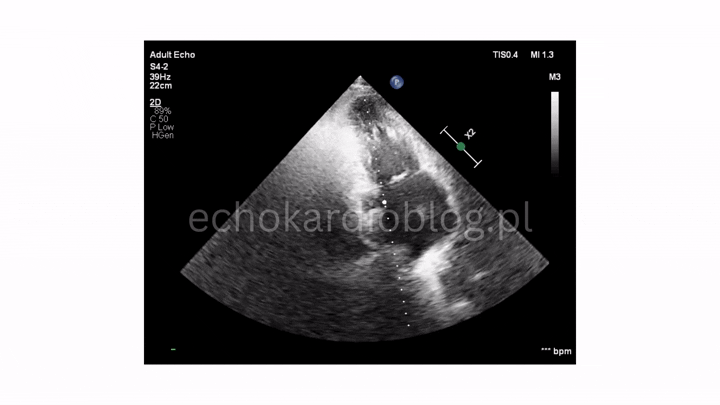

w projekcji – podmostkowej 4 jamowej uwidoczniono wegetacje na zastawce trójdzielnej i mitralnej